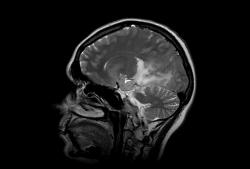

Женщина 47 лет, в течении долгого времени страдала от головных болей. В последние несколько месяцев - прогрессирующая потеря зрения (на оба глаза).

T2 ВИ Sagittal

Presented images are corresponded for cerebral (right temporal-occipital region) neoplasia; high grade glioma is most suggested.

Глиальная опухоль.